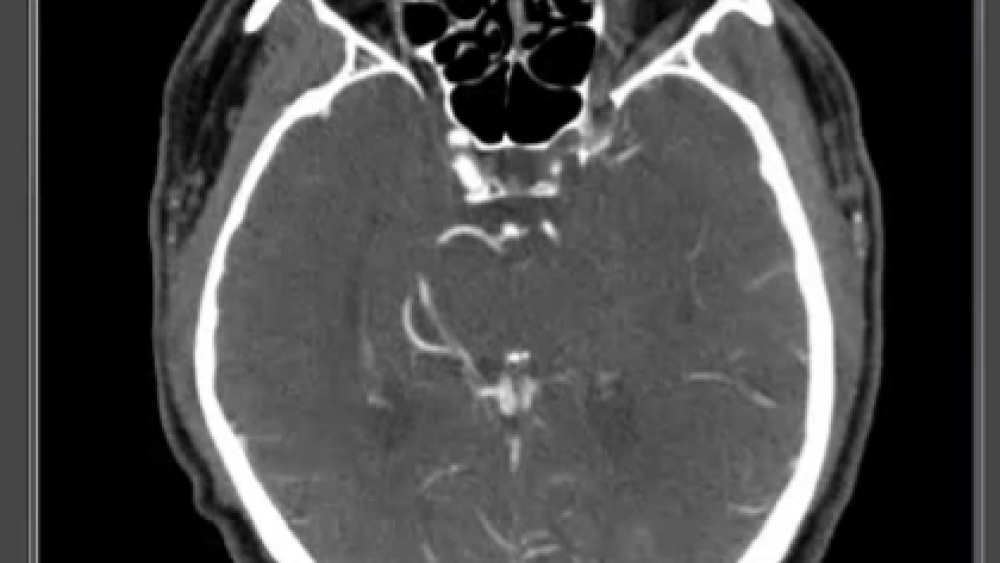

The Joint Commission on Accreditation of Healthcare Organizations (JCAHO) currently identifies three levels of stroke center. (4) The first, an Acute Stroke Ready Hospital (ASRH), is any facility that has 24/7 CT capabilities and can initiate tPA. CT is required to differentiate ischemic strokes from hemorrhagic strokes, to determine patient eligibility for tPA and is the only non-invasive procedure that can conclusively diagnose LVO. Training for ED staff at an ASRH is only required twice per year and core stroke team members must receive only four hours of training annually.